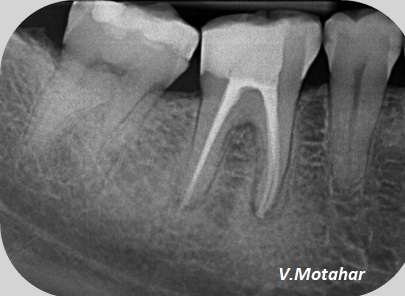

Root Canal treatment on Lower molar tooth immediate after the Root Filling!

before

after